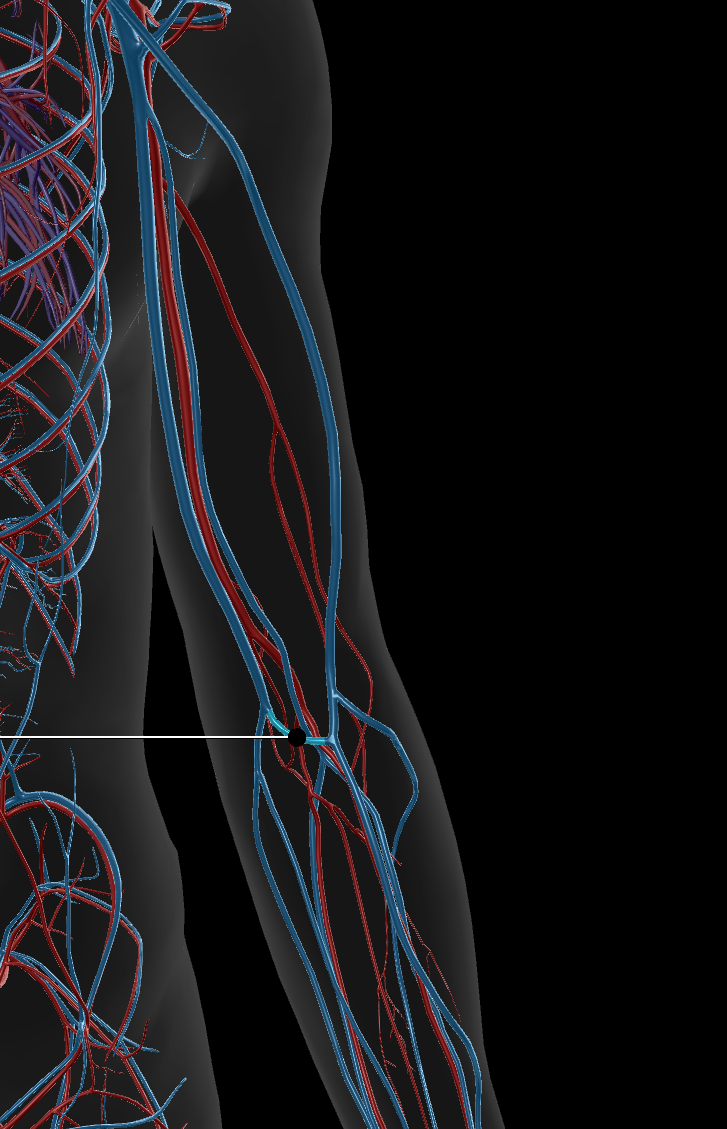

Femoral Artery

Popliteal Artery

Femoral Vein

Popliteal Vein

Great Saphenous Vein

Deep Femoral Artery